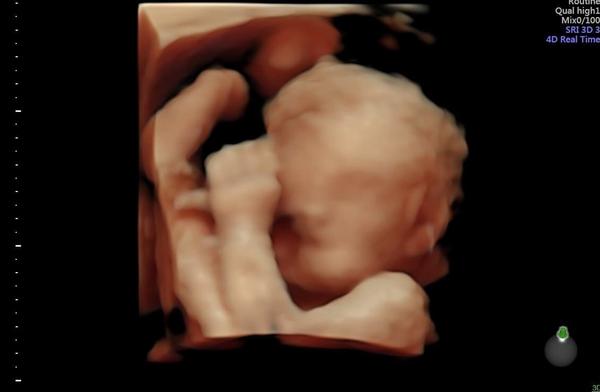

My byli na 3D/4D na konci 28.tt a syn byl obličejem otočený směrem do břicha. Čtvrt hodiny mi doktor třepal s břichem, ať se milostpán pohne. Kdeže 😂. Odcházeli jsme s touto fotkou, víc se nenatočil.